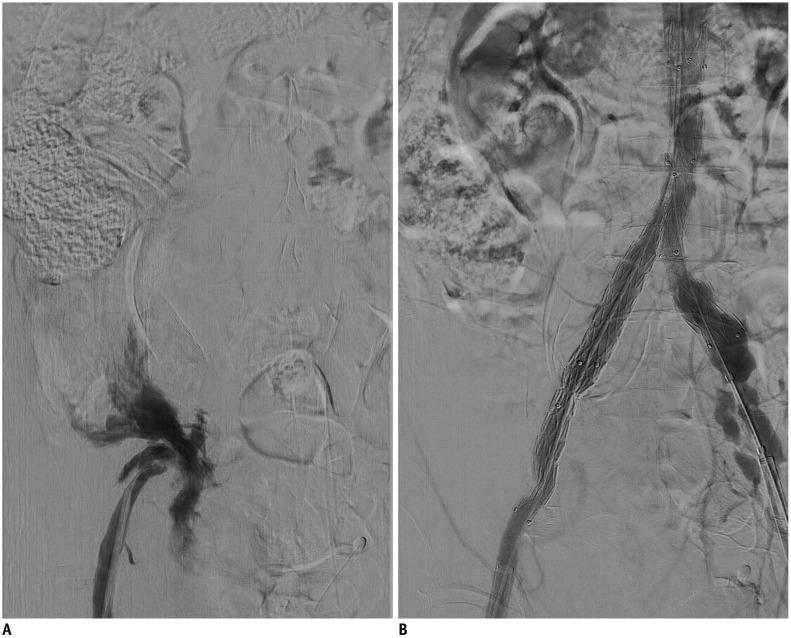

Abdominal aortic aneurysm (AAA) can be defined as an abnormal, progressive dilatation of the abdominal aorta, carrying a substantial risk for fatal aneurysmal rupture. Endovascular aneurysmal repair (EVAR) for AAA is a minimally invasive endovascular procedure that involves the placement of a bifurcated or tubular stent-graft over the AAA to exclude the aneurysm from arterial circulation. In contrast to open surgical repair, EVAR only requires a stab incision, shorter procedure time, and early recovery. Although EVAR seems to be an attractive solution with many advantages for AAA repair, there are detailed requirements and many important aspects should be understood before the procedure. In this comprehensive review, fundamental information regarding AAA and EVAR is presented.

腹主动脉瘤(AAA)可定义为一种腹部主动脉的异常、进行性扩张,具有致命性的动脉瘤破裂的巨大风险。AAA 的血管内修复术(EVAR)是一种微创的血管内手术,涉及在 AAA 上方放置分叉或管状支架移植物,将动脉瘤从动脉循环中排除。与开放手术修复相比,EVAR 仅需要一个刺切口、更短的手术时间和更早的恢复。尽管 EVAR 对于 AAA 修复似乎是一种具有许多优势的有吸引力的解决方案,但在进行该手术之前,需要了解详细的要求和许多重要方面。在本全面综述中,介绍了关于 AAA 和 EVAR 的基本信息。